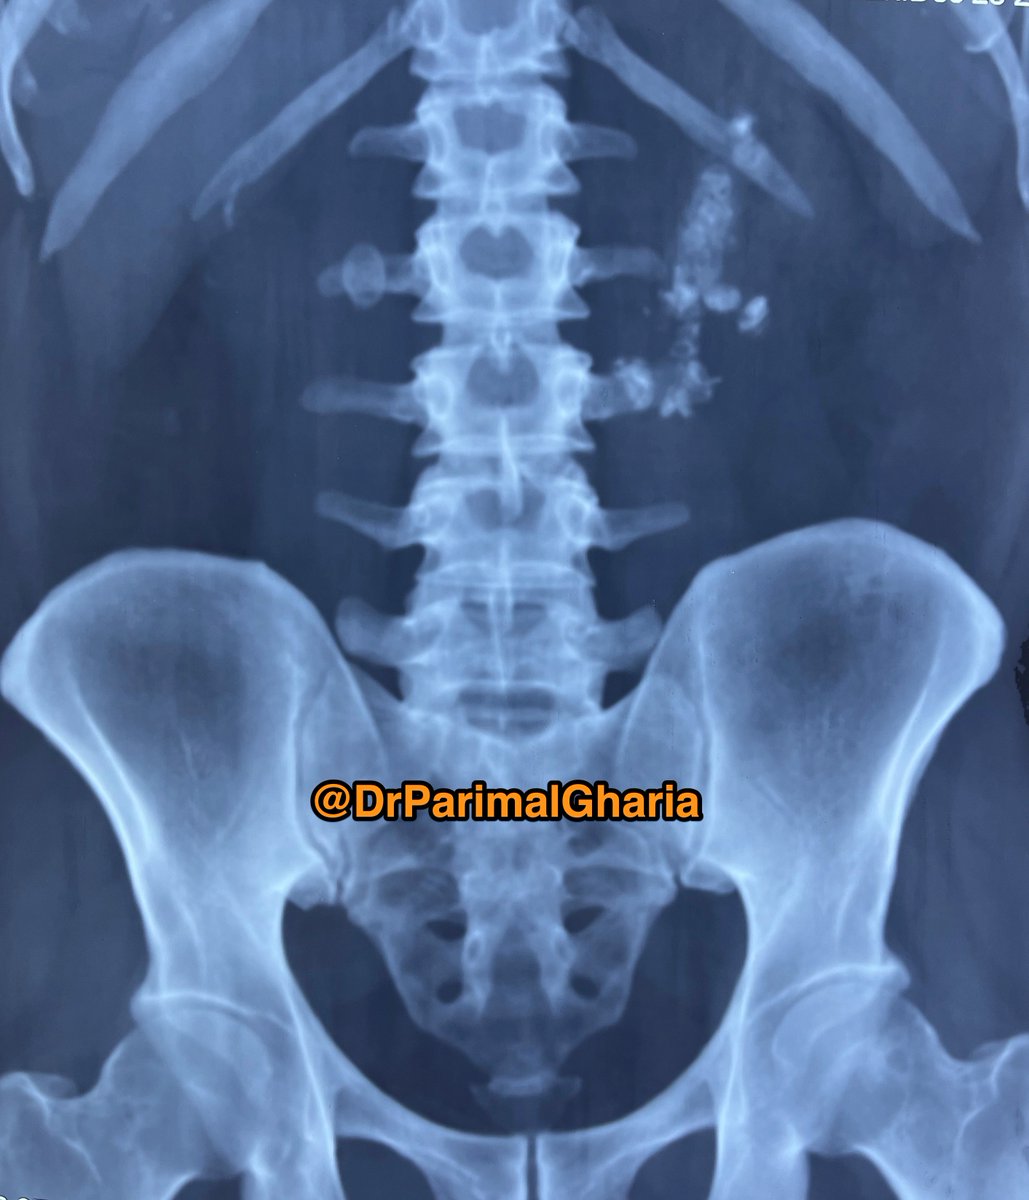

Bladder Mass or Cystitis? #Cystoscopy